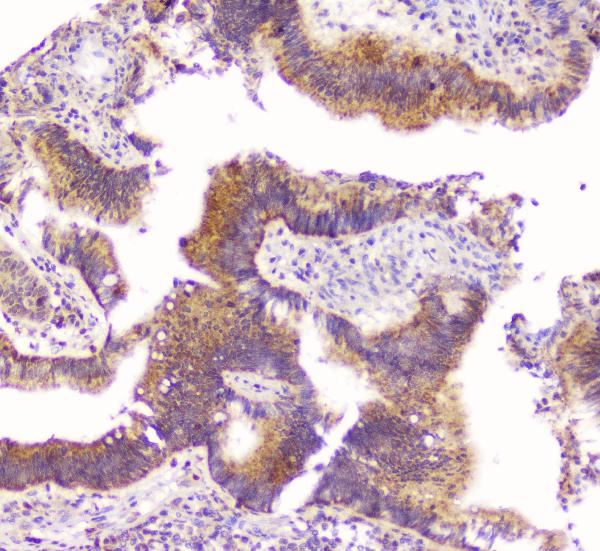

IHC analysis of OPG/TNFRSF11B using anti-OPG/TNFRSF11B antibody (A00863).

OPG/TNFRSF11B was detected in a paraffin-embedded section of human rectal cancer tissue. Biotinylated goat anti-rabbit IgG was used as secondary antibody. The tissue section was incubated with rabbit anti-OPG/TNFRSF11B Antibody (A00863) at a dilution of 1:200 and developed using Strepavidin-Biotin-Complex (SABC) (Catalog # SA1022) with DAB (Catalog # AR1027) as the chromogen.